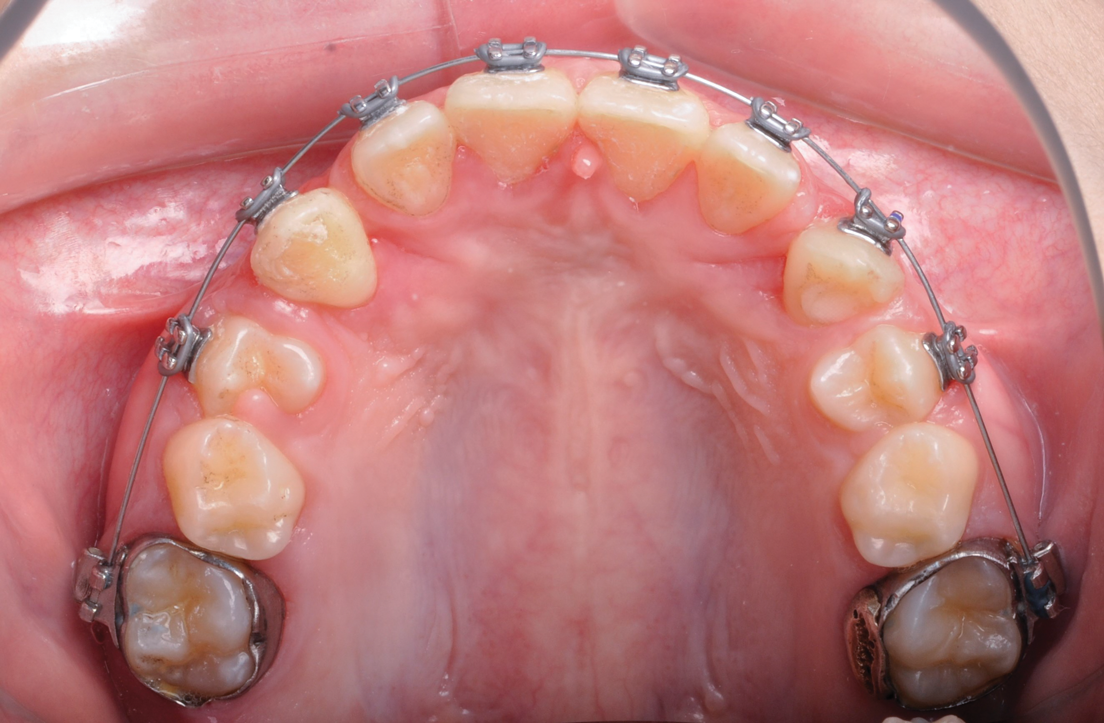

Fig 2 scans of palatal impacted canines; front view (Fig 2) and occlusal view (Fig 3).

Figure 2

Fig 3. CBCT scans of palatal impacted canines; front view (Fig 2) and occlusal view (Fig 3).

Figure 3